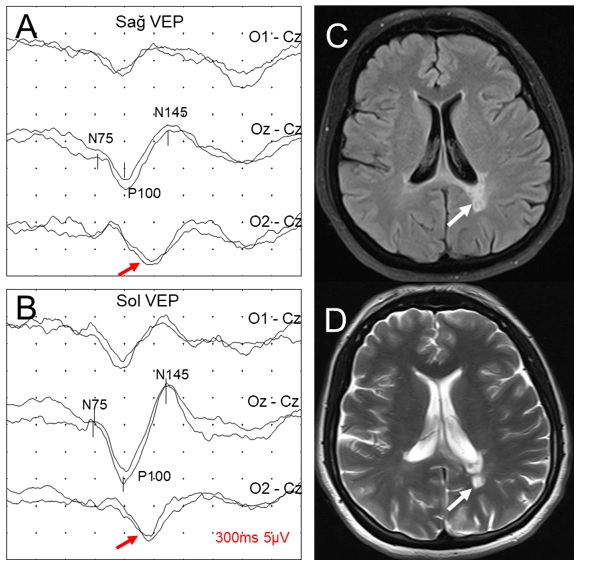

Şekil 7. Dengesizlik ve ellerde titreme

yakınması olan 22 yaşındaki multipl skleroz tanılı

kadın hastanın patern VEP incelemesi (A, B) ve

aksiyal planda FLAIR (C) ve T2 (D) MR

kesitleri. Sol oksipital bölgede, lateral ventrikül

arka boynuzuna komşu, subkortikal hiperintens lezyon

görülmektedir. Patern VEP incelemesinde, hem sağ hem

sol göz uyarımıyla orta hat ve sol oksipital

bağlantılarda (Oz-Cz ve O1-Cz), P100 latansları normalken, sağ oksipital bağlantılarda (O2-Cz)

P100 latansları uzundur (çaprazlaşmamış asimetri, retrokiazmatik lezyon).